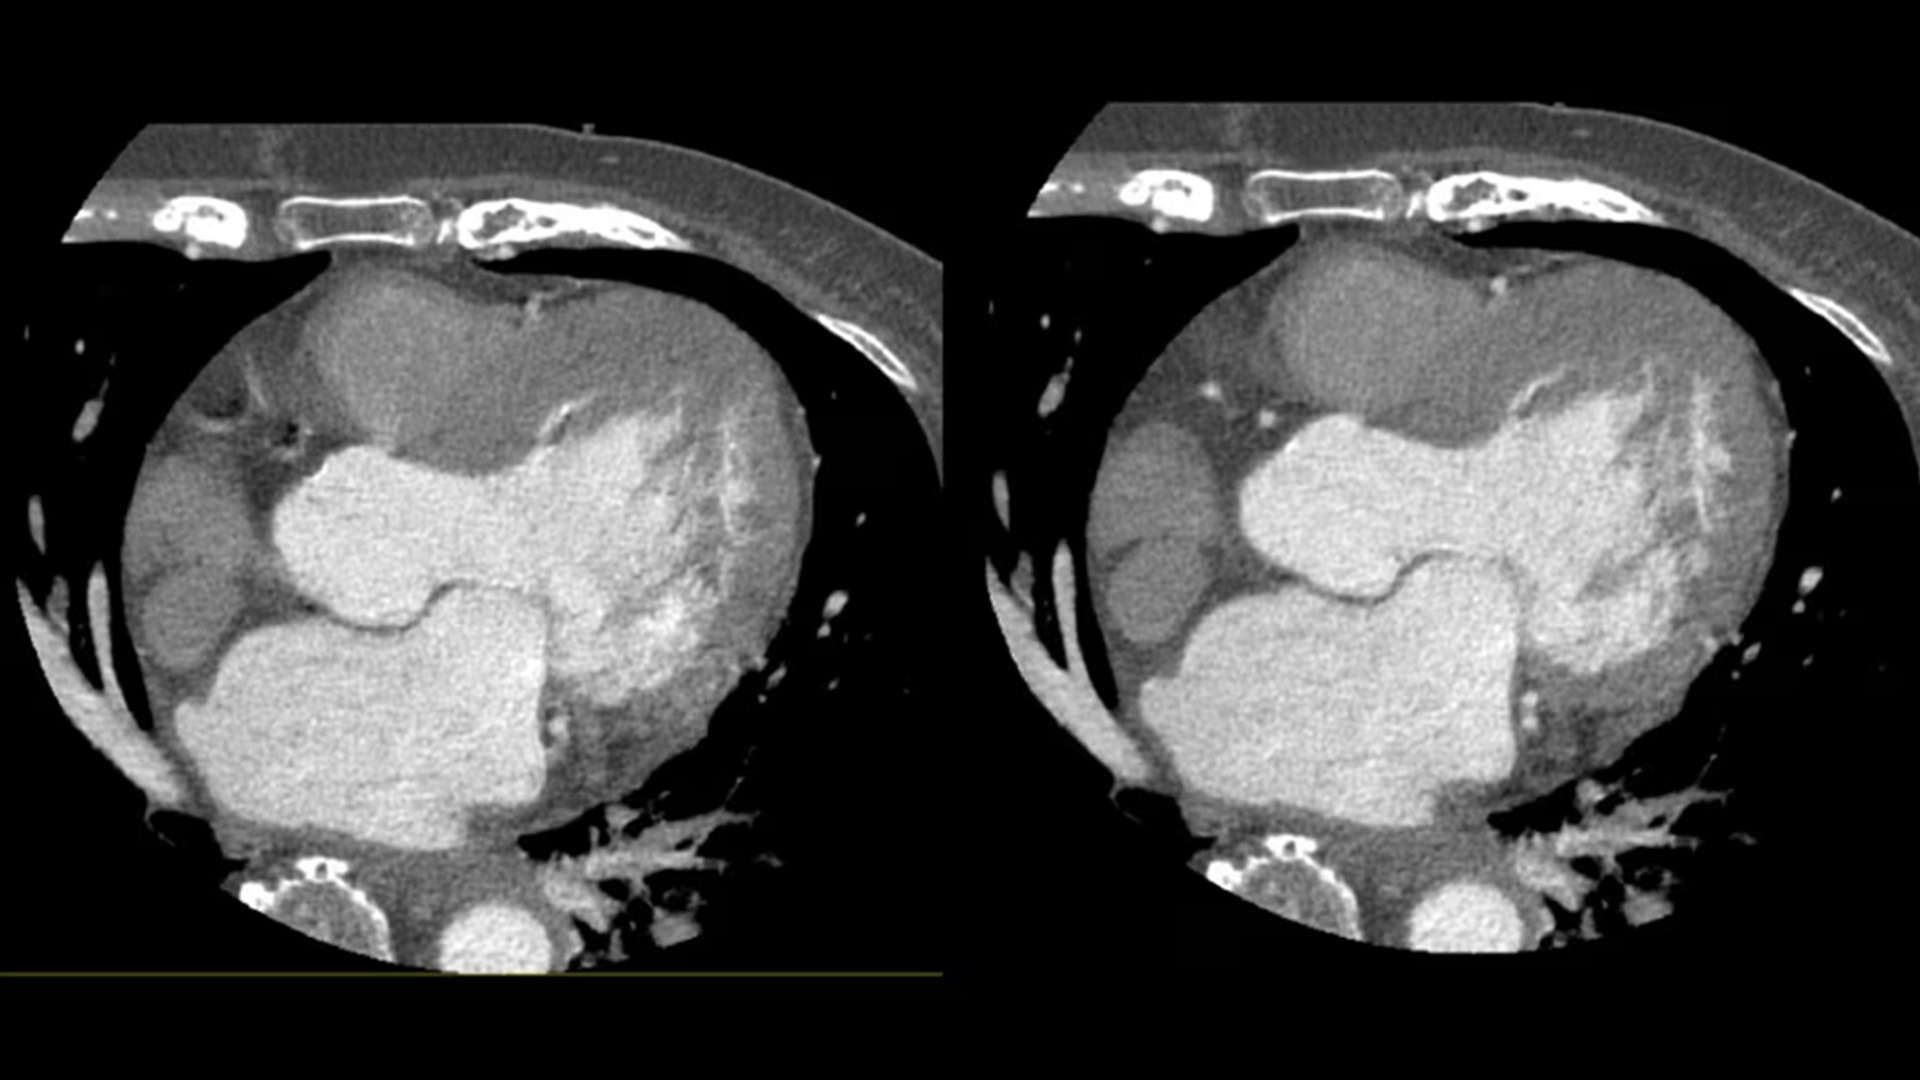

SnapShot Freeze 2

Intelligent and automated whole-heart motion correction for enhanced Cardiac CT imaging.

Motion correction

6x reduction in motion artifacts1